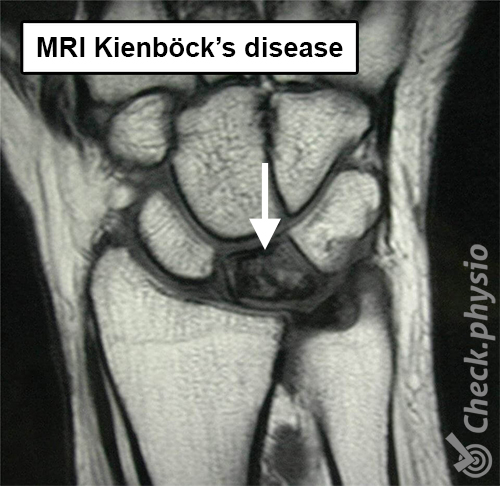

If an X-ray is taken in the early stages of the disease, it often does not yet show any abnormality. In this case, an MRI can provide more clarity. However, an X-ray at a later stage can show the condition of the lunate bone.